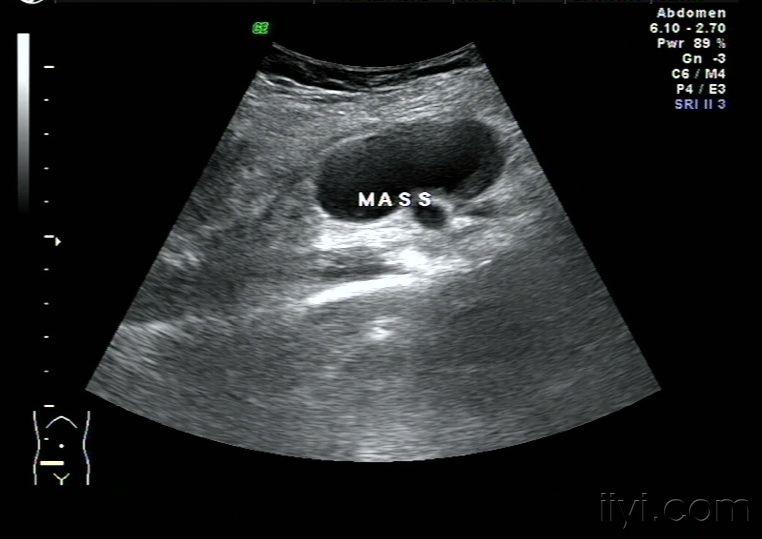

囊肿和实质性肿块的声像图比较 肝囊肿 肝肿瘤